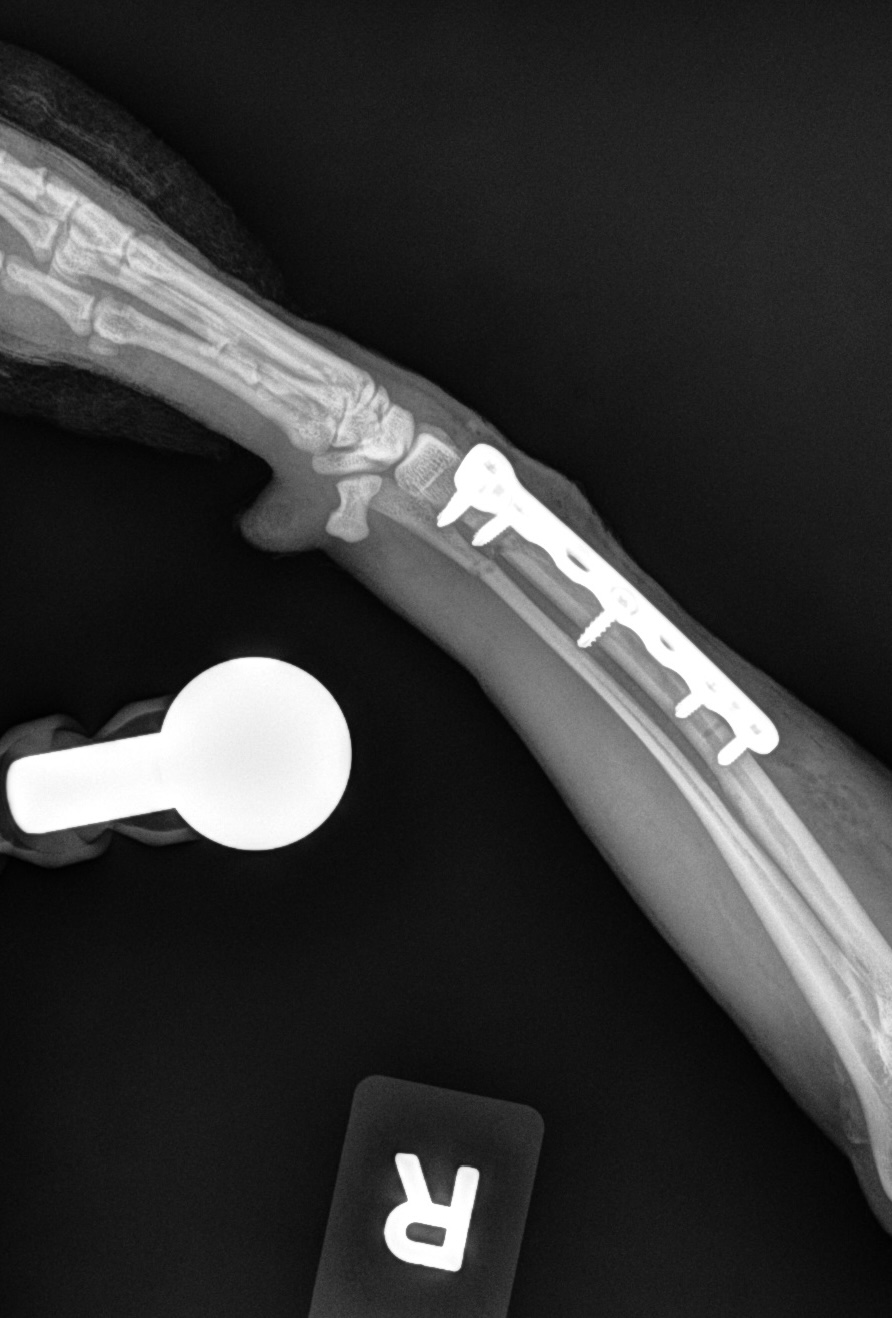

Fracture Repair

We provide surgical fracture repair for many types of broken bones. Treatment plans are individualized based on the location and complexity of the fracture, your pet’s age and size, and overall health.

Large Dog Radius Fracture Before

Large Dog Radius Fracture After #1